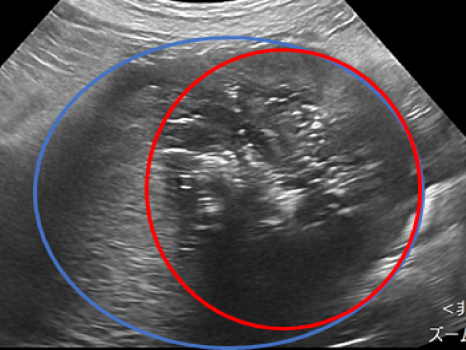

外側左葉に63.3㎜×61.5㎜の肝臓腫瘍が認められ細胞診にて肝細胞癌と診断されたました。 摘出も可能でしたが高齢であり、過去に何度か開腹手術もしており、甲状腺がんの摘出も同時に手術を行うため負担の少なさを考慮しフュージョンイメージングを用いてアブレーションを実施しました。 超音波ガイド下で肝臓腫瘍の周囲に生理食塩水を満たすことで周囲の組織を熱で損傷することなく安全に実施が可能です。 術後の経過も良好で次の日に退院しました。

アブレーション実施の様子

超音波を当てながらアンテナ(青矢頭)を挿入している

アブレーション実施中の超音波画像

アンテナ(青矢頭)と焼灼されているところ(赤丸)